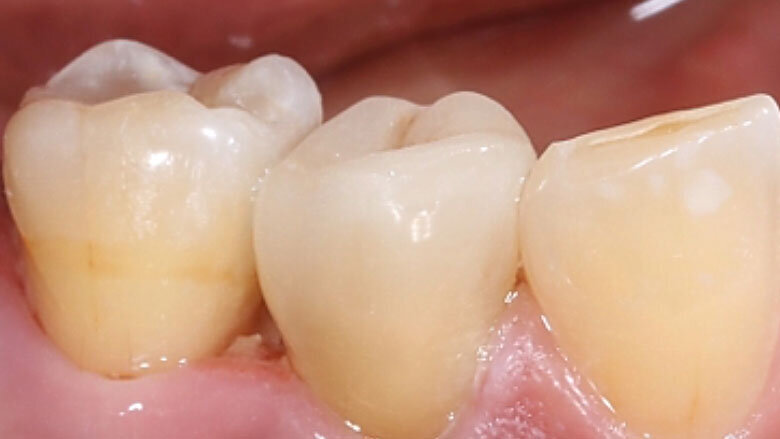

Fig. 11. La restauración de cerámica de feldespato durante la prueba clínica en boca.

Fig. 12. Desde vestibular no se observaban transiciones entre la restauración y el diente.

Acto seguido se diseñó digitalmente la endocorona y se confeccionó a partir de VITABLOCS Mark II mediante la unidad de fresado MyCrown Mill (FONA Dental, Bratislava, Eslovaquia). Tras la separación del conector se llevó a cabo la prueba en boca de la restauración y a continuación se realizó su acabado cuidadoso con un diamante fino. Posteriormente se procedió a la caracterización de las fosas con VITA AKZENT Plus EFFECT STAINS (ES06, rojo óxido) y al glaseado final. Dado que una unión adhesiva fiable a la sustancia dental es un factor clave para el éxito clínico a largo plazo, se colocó un dique de goma para garantizar la ausencia de contaminación y la sequedad absoluta.

Acondicionamiento y colocación

Se grabó la cerámica de feldespato con ácido fluorhídrico para crear un patrón de grabado microrretentivo y a continuación se silanizó. Se acondicionó la cavidad con ácido fosfórico y un adhesivo. Para la fijación adhesiva se calentó el composite Micerium (Micerium, Avegno, Italia) en el color UD2, a fin de fluidificarlo para la inserción. Tras la fotopolimerización y la eliminación de los restos de composite, la restauración se integró perfectamente en la sustancia dental natural gracias a sus excelentes propiedades fotoópticas.